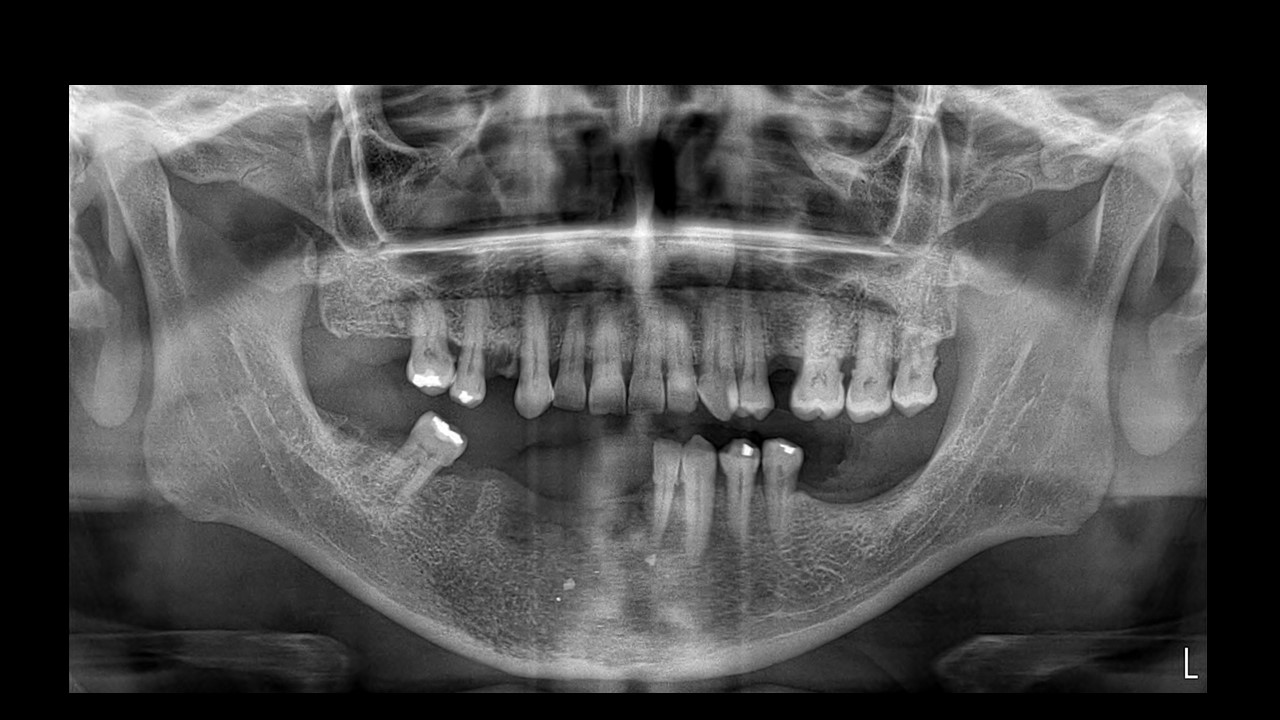

Figura 1

En la radiografía panorámica (Figura 1) se observa alteración del patrón ósea trabecular en la zona sinfisiaria, parasinfisiaria y cuerpo mandibular derecho; caracterizada por la disminución de la densidad ósea, lechos alveolares difusos correspondientes a piezas 31, 41, 42, 43, 44, 45; sin preservación de lámina dura; zonas irregulares de erosión de la cortical del reborde basal mandibular; así mismo se aprecia imágenes radiopacas irregulares sugerentes de restos de material restaurador.